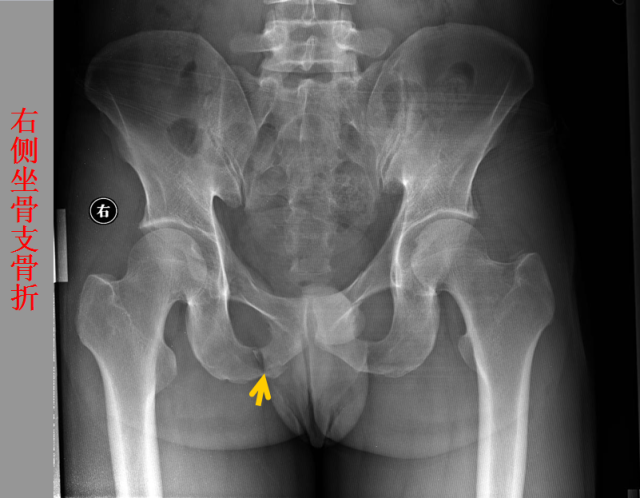

骨折篇

01

定义:骨折{Fracture}是指骨的完整性和连续性的折裂或粉碎。包括创伤性骨折、疲劳性骨折和病例理性骨折。 临床上以创伤性骨折*常见。